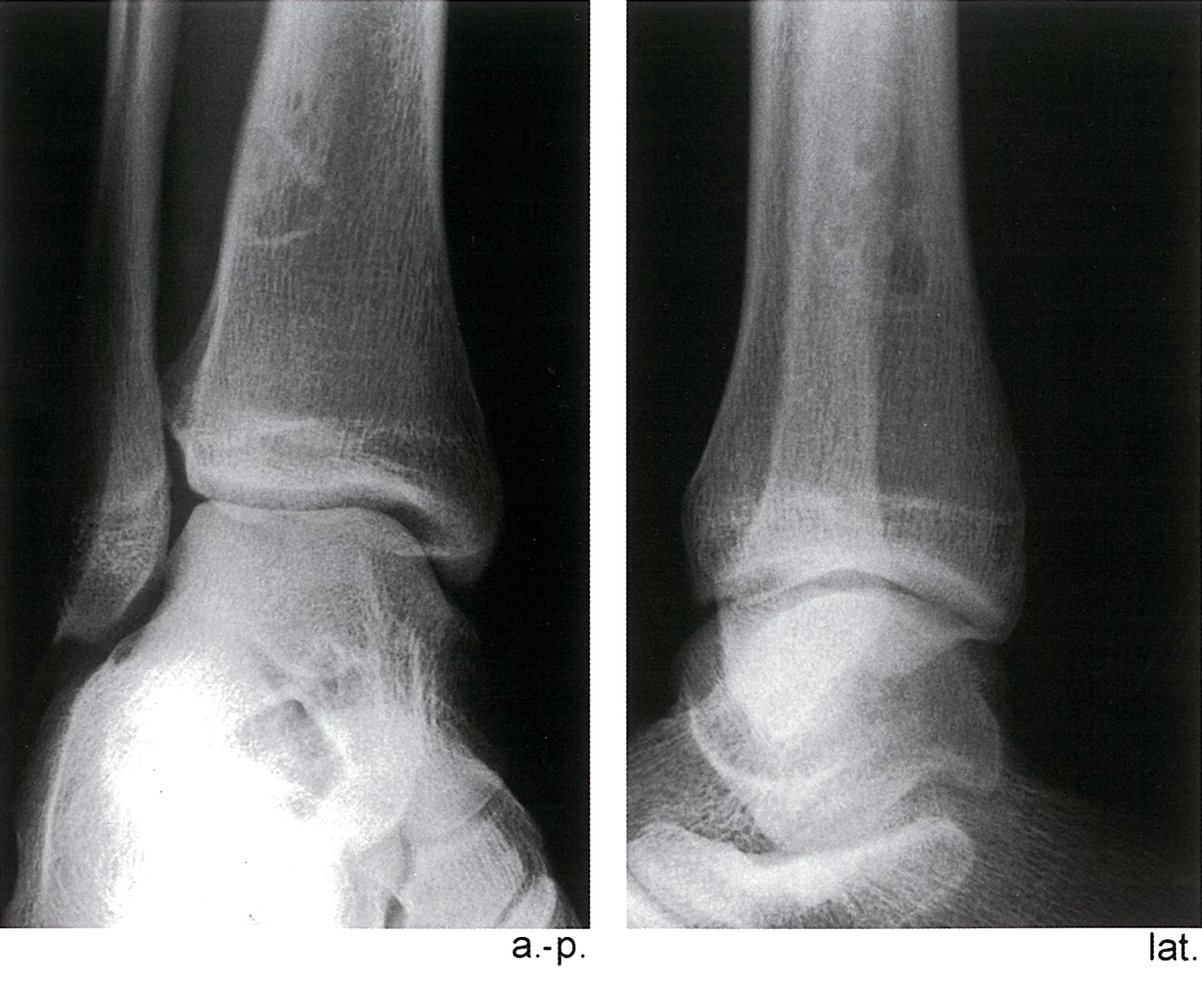

• Description: benign but locally aggressive tumor composed of giant cells that arise from the bone marrow [1]

• Epidemiology: peak incidence between 20 and 40 years

• Clinical features

• Found in the epiphysis or metaphysis of long bones (especially knee region)

• Pathological fractures

• Local pain and swelling

• Limited range of motion

• Diagnostics

• X-ray: multicystic osteolytic lesions (soap-bubble appearance)

• Histopathology

• Mononuclear, RANKL-expressing cells (neoplastic)

• Multinucleated giant cells (are reactive and resemble osteoclasts)

• Treatment: curettage and bone grafting or en-bloc resection to minimize recurrence rate

• Prognosis: risk of malignant degeneration increases with age; may spread to the lungs